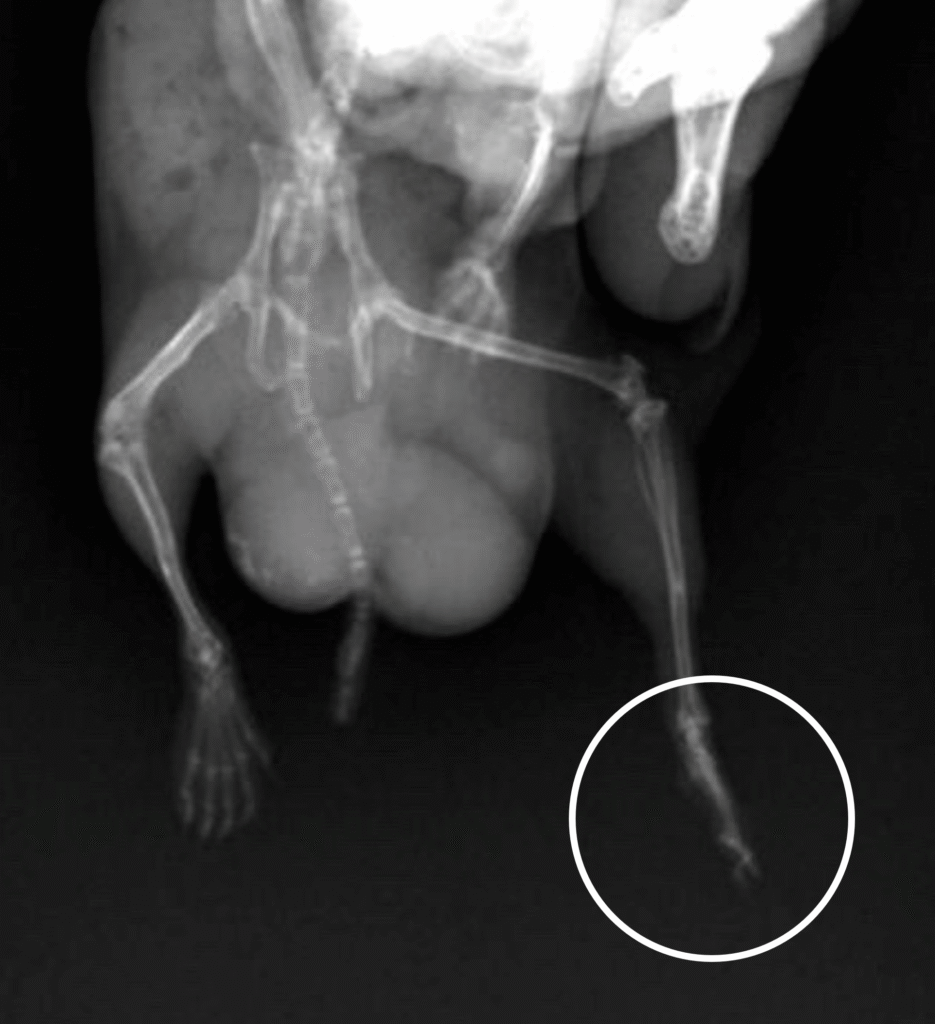

The x-ray showed damage to his toes, and the vet explained that Picco was chewing his paw, likely from the stress of the surgery and having the cone on, and because of the initial cut to his paw. She believed that necrosis was likely to occur and that Picco would need an amputation to stop it from spreading, but was unable to make a decision or perform the surgery herself. We had to wait for the surgical vet (the doctor who removed Picco’s tumor) to take a look the next day when he was on duty.

Despite checking on Picco periodically throughout the night, he still managed to chew on his paw until there was exposed bone. Worried, I took him back to the hospital and the doctor regrettably confirmed that Picco would need an amputation after all.

The doctor amputated up to Picco’s knee, as removing just the paw would’ve meant exposed bone that could easily get injured. Necrosis had also started to set in so it was good that Picco was brought in quickly; we were shocked at how quickly and suddenly necrosis had spread, seeing as the injury was healing well just the night before when Picco got discharged.